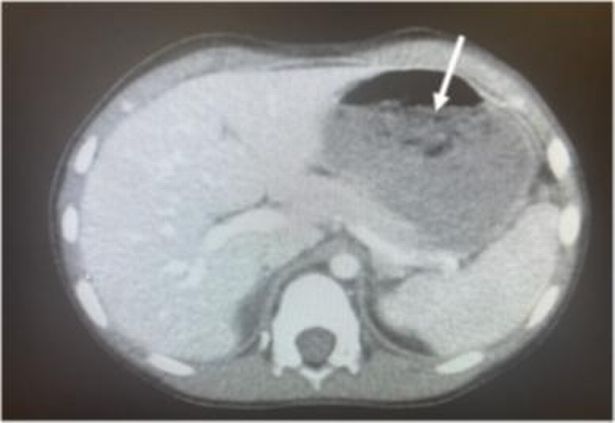

Un copil de doar 5 ani a fost adus de urgență la un spital din statul Ohio, SUA, deoarece acuza dureri mari de burtă și diaree. Medicii au început imediat investigațiile, inclusiv o radiografie abdominală. Așa au descoperit medicii că în stomacul micuțului se ascundea un bulgăre de gumă de mestecat.

Potrivit greatnews.ro, cu o zi înainte, băiatul a înghițit aproximativ 40 de bucăți de gumă de mestecat, într-un moment de neatenție din partea părinților.

Astfel, medicii i-au introdus copilului pe gât un tub de metal, apoi au folosit un forceps pentru a apuca bulgărele de gumă și pentru a îl extrage.